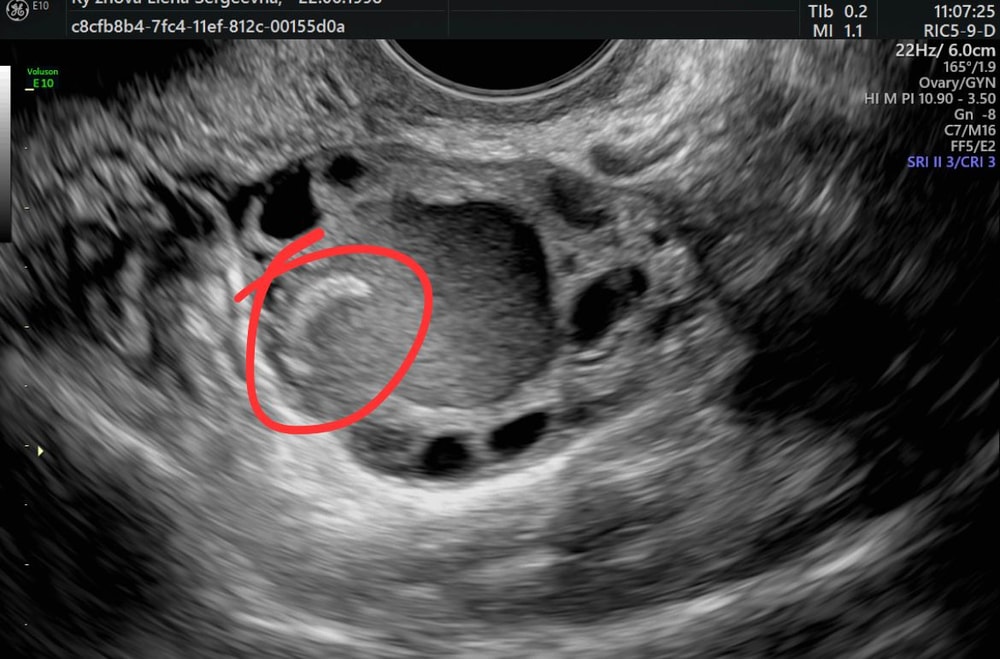

"На УЗИ-снимке врач описывает два жидкостных образования: 7 мм и 25 мм. Образования с мелкодисперсной взвесью - это как раз эндометриоидные кисты. Тот гиперэхогенный компонент, который Вы выделили на снимке, это пристеночное гиперэхогенное аваскулярное образование в составе эндометриоидной кисты. Такие образования бывают очень часто, это не дермоидная киста.

Это структура эндометриоидной кисты, это киста с высокой степенью воспалительной активности, так как там пристеночно образуется фиброзный компонент. Это говорит о том, что даже если Вы не лечите эту кисту, все равно овариальный резерв со временем снижается на фоне выраженного воспаления. Не рекомендуется сейчас удалять кисту даже при высоком овариальном резевре. Во-первых, потому что он сильно снижается в 95% случаев при образованиях такого вида и такого размера. Во-вторых, сама операция способствует распространению эндометриоза, двустороннему поражению, т.е. может перейти на другой яичник. Также в период планирования беременности есть риск рецидива. На практике мы часто сталкиваемся с такими проблемами.

Okey google, да недавняя находка, до этого думаю были маленькие было не видно, одна запреметила полтора года назад, врач думала что киста эндометриозная, меньше см. При планировании видимо начали расти, их2 шт теперь. Одна 2,5 другая почти см. Я сравнила узи и заметила что подросили с мая . Думаю скажут удалять. А у вас была тератома внутри яичника или снаружи?да я слышала что появляются они заново …а вы ощущали кисту? Было такое ощущение как будто застудили яичники?